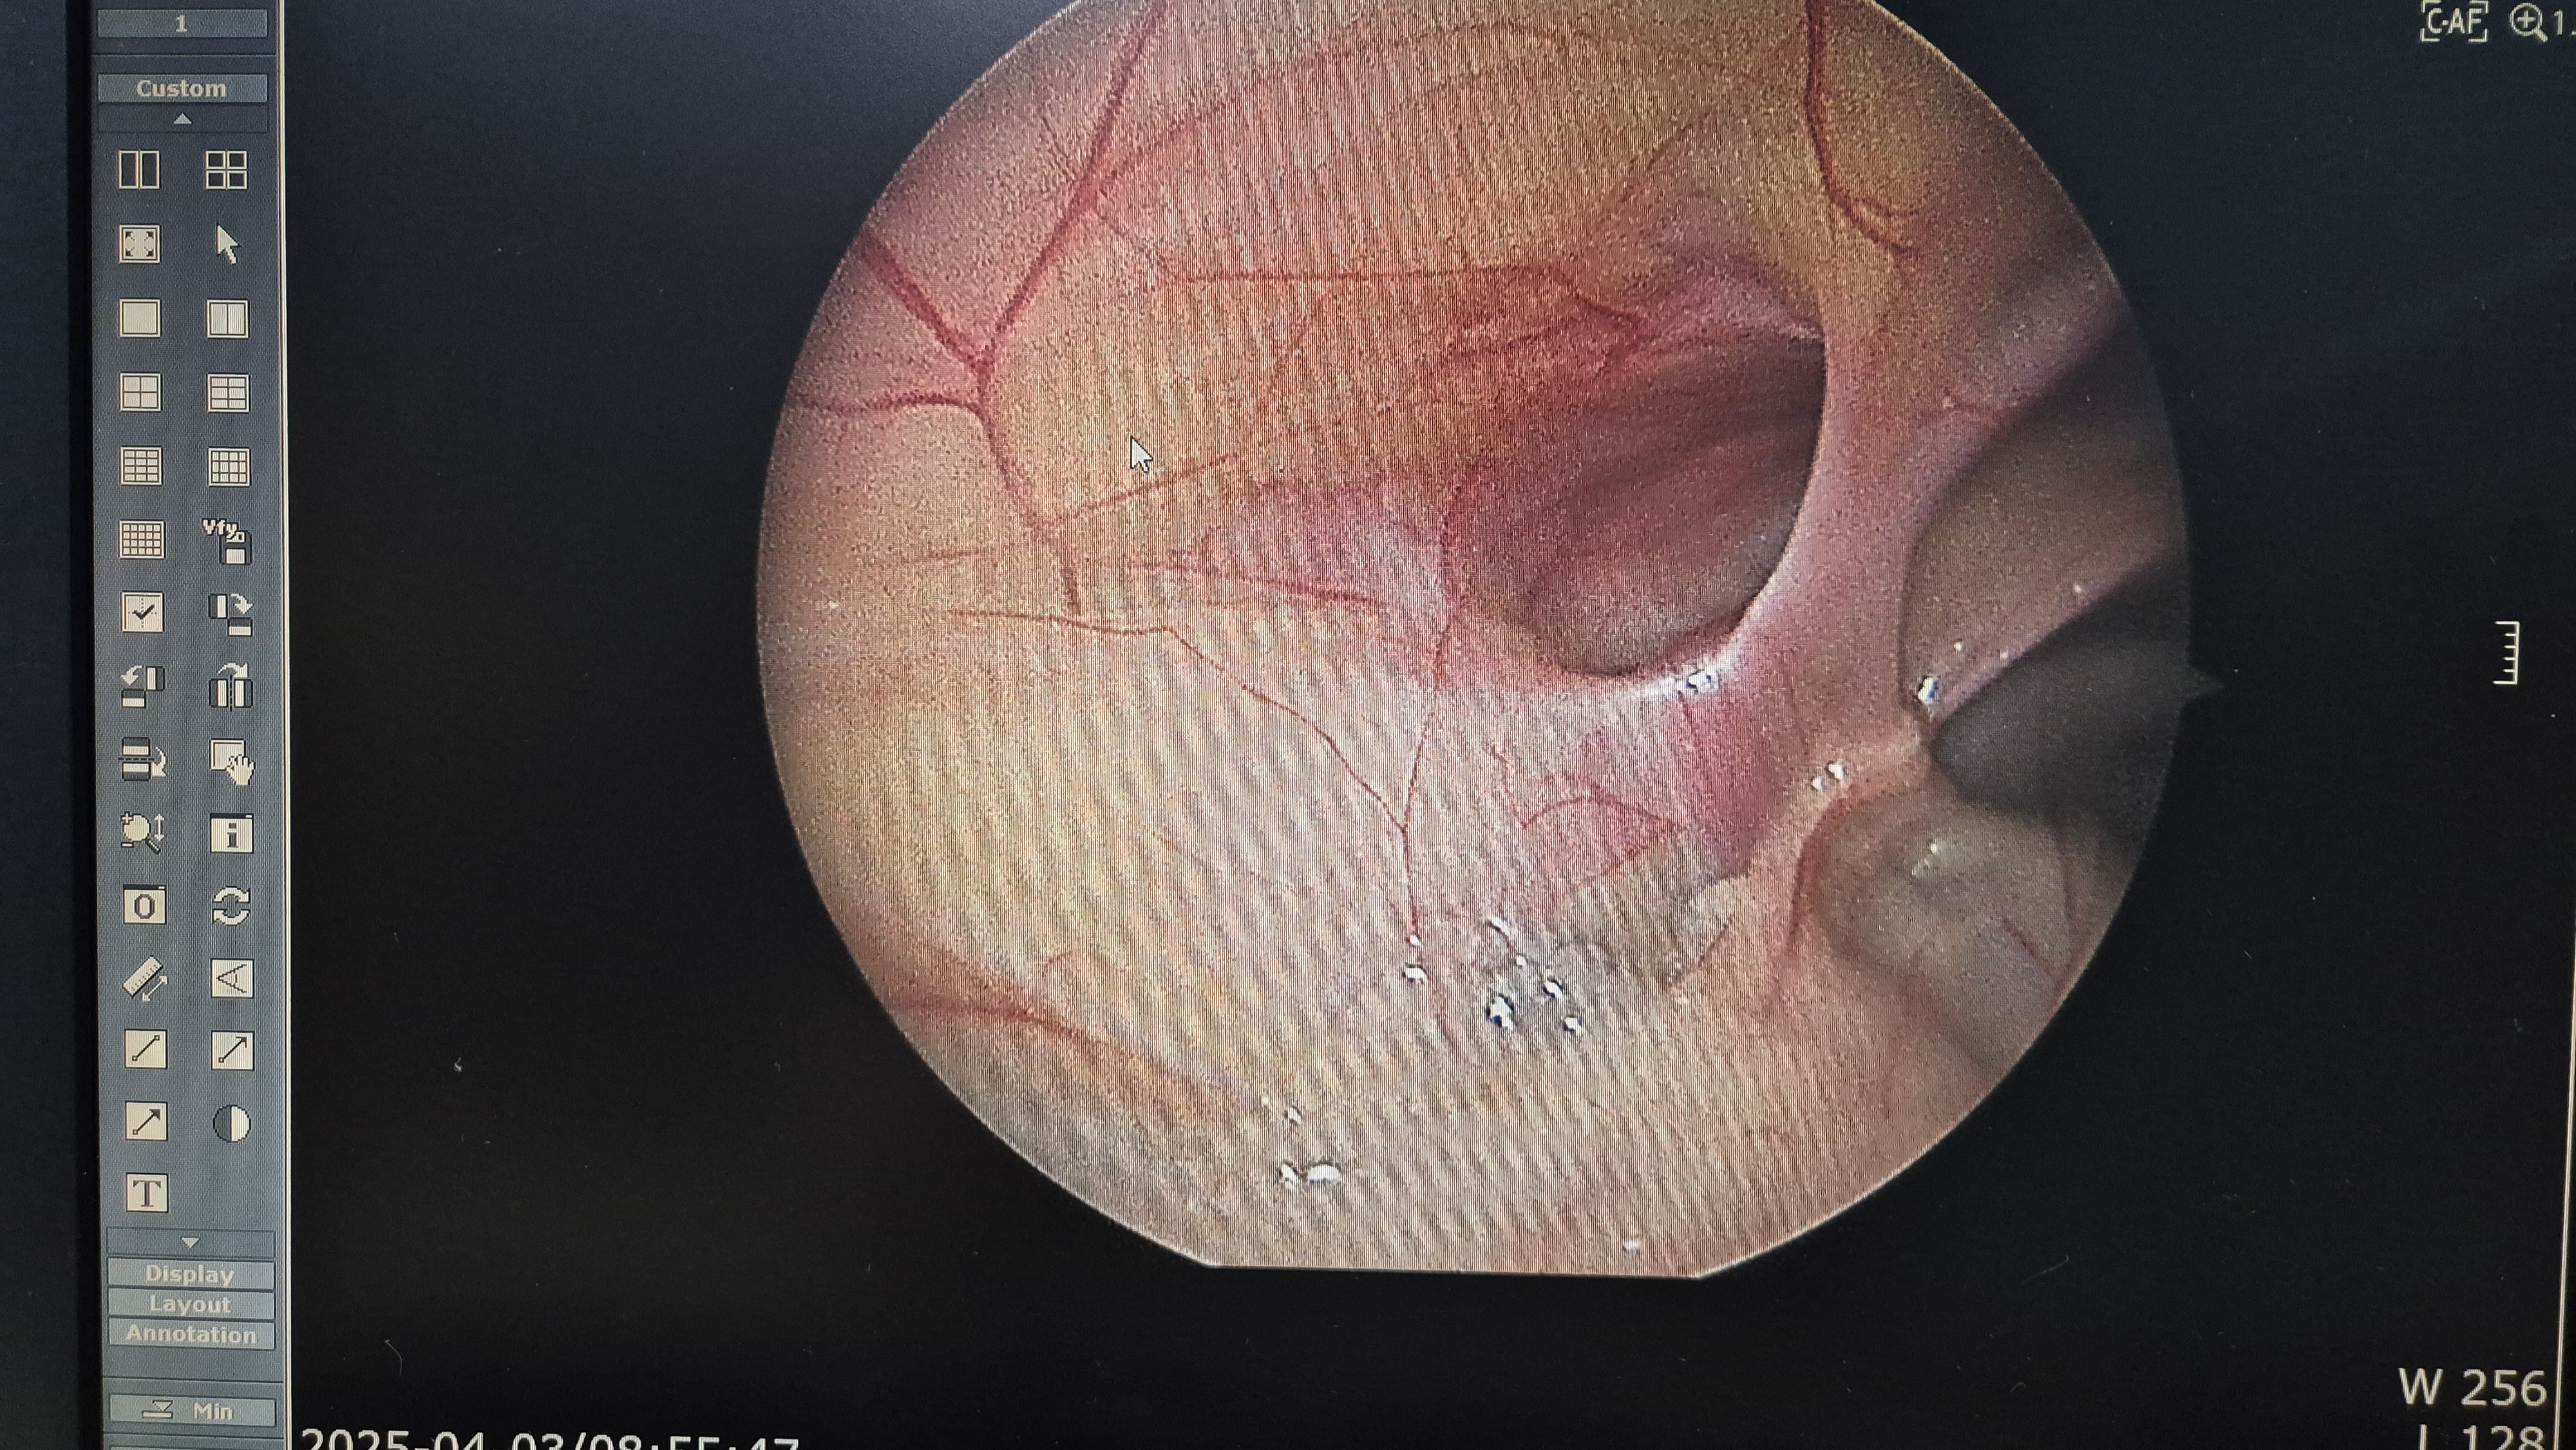

좌측 서혜부 탈장.